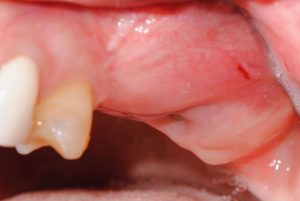

Estas son las imágenes obtenidas en la Exploración intraoral inicial:

- La paciente no soportaba las coronas antiguas sobre implantes, porque apoyaban sobre mucosa alveolar y no sobre encía queratinizada, invadiendo el espacio biológico.